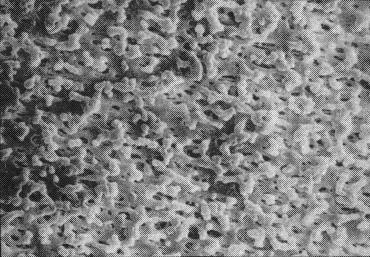

16.セパラックスの電顕写真

実は、最初のセパラックスの特徴は電子顕微鏡で見ると穴の大きさがバラバラなのです。他の膜に比べてみましても。

それで分離される血清蛋白が、M蛋白が非常に粘ちょうになると、だんだん電気泳動で細いバンドに集約されますから、後程申しますように蛋白が濃縮されれば濃縮されるはど、ベトベトになるので、膜の上で小さな穴の所にひっかかって、穴の大きな所だけ、先へちょっと進むので、ああいう波形帯を示すわけです。